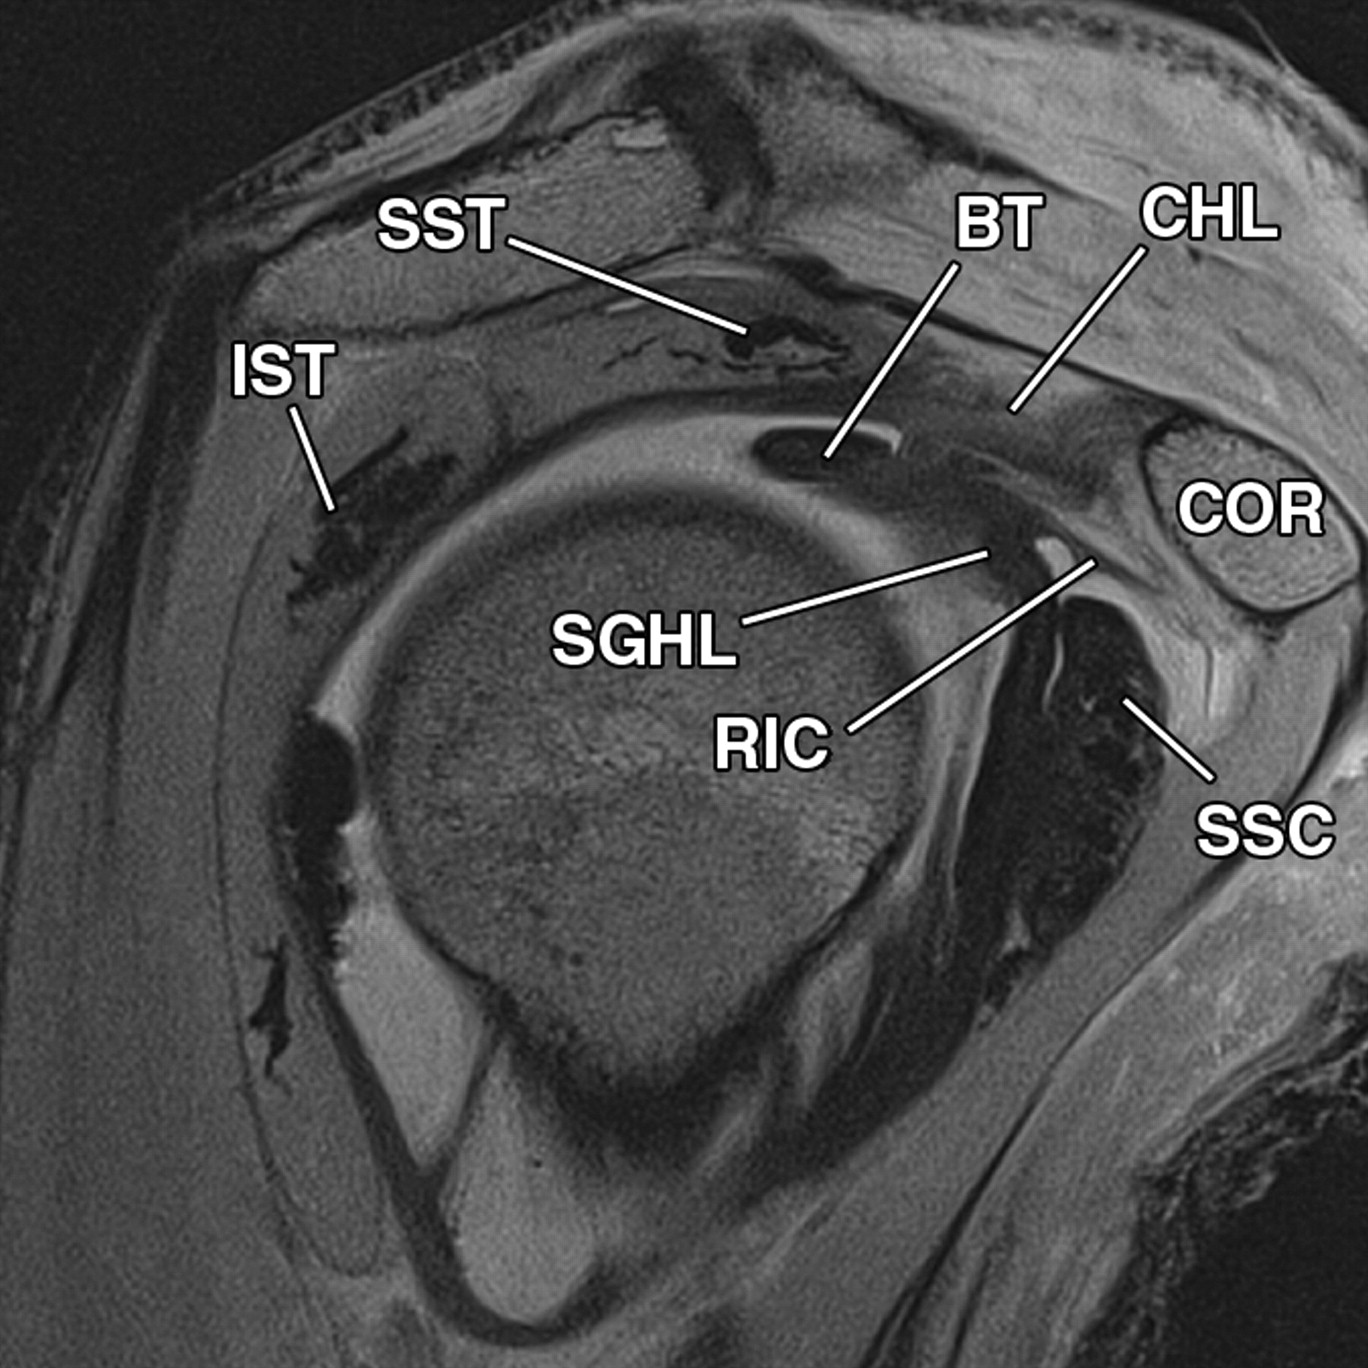

What Is The Best Imaging For Rotator Cuff Injury